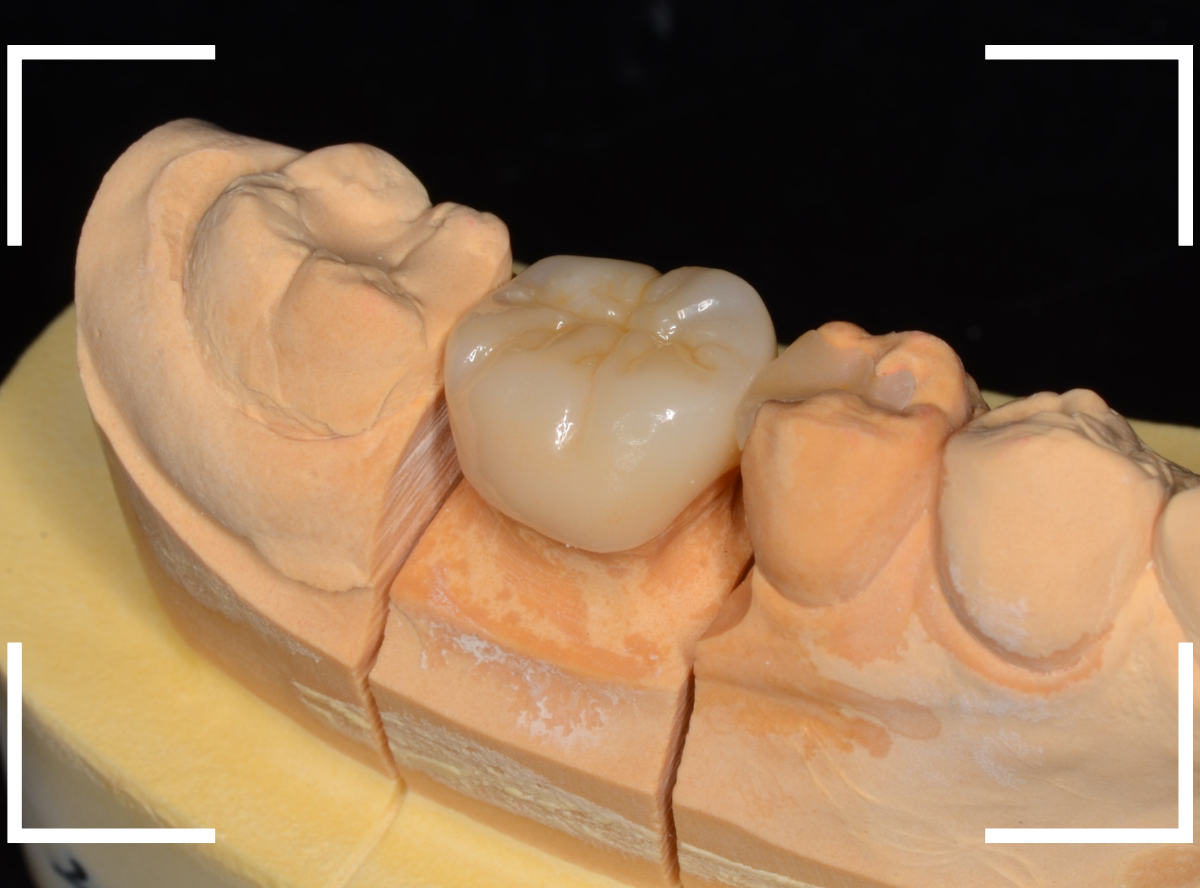

仮歯でしばらく経過観察し、症状がないのを確認した後に、型どりをして(オール)ジルコニア・クラウンを製作しました。

お口の中でジルコニアに置き換えた後も、特に症状なく経過されているようで、ホッとしました。